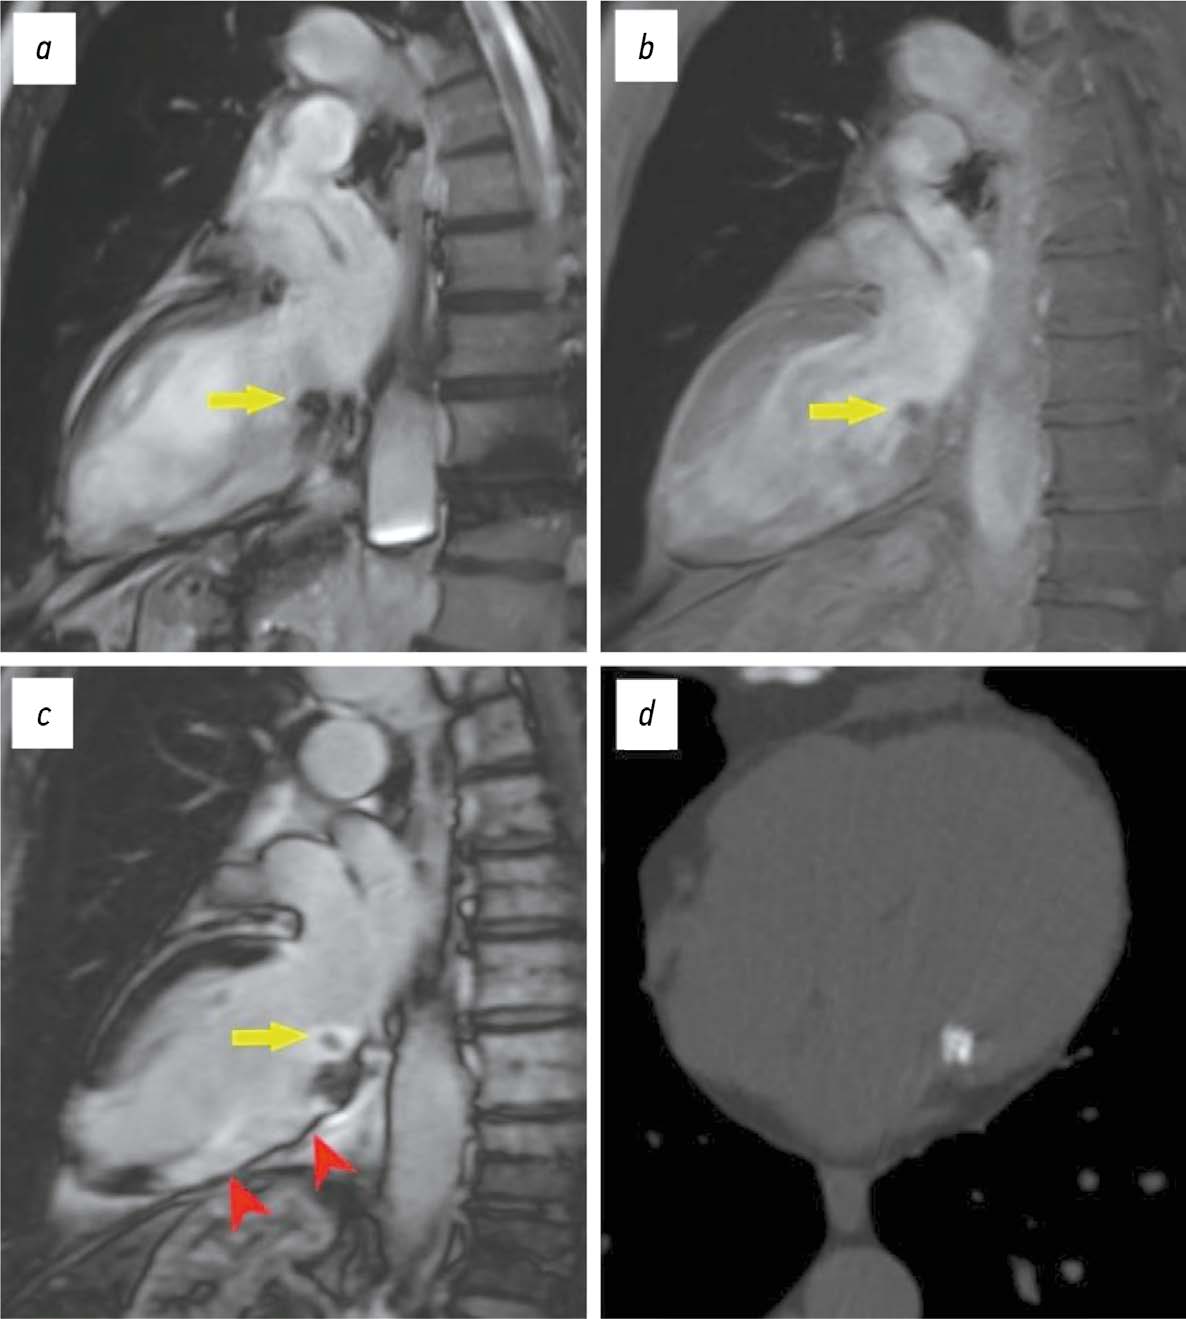

BACKGROUND: Cardiac amyloidosis is a serious progressive disease with a high mortality rate. The differential diagnosis of cardiomyopathies due to amyloid light-chain (AL) amyloidosis and transthyretin (ATTR) amyloidosis is important for selecting the optimal treatment strategy.

MATERIALS AND METHODS: A retrospective analysis of the medical records of 25 patients with a confirmed diagnosis of amyloid cardiomyopathy was performed. Patients were divided into two groups according to the type of amyloidosis, with group 1 including patients with cardiomyopathy due to AL amyloidosis and group 2 including patients with cardiomyopathy due to ATTR amyloidosis. All patients underwent contrast-enhanced cardiac magnetic resonance imaging. Volumetric and linear cardiac parameters, ventricular function, and late gadolinium enhancement patterns were assessed. Standard statistical methods were used, and differences were considered significant at p <0.05.

RESULTS: Group 2 showed a more significant thickening of the myocardial walls compared to group 1 (interventricular septum: 18 [17; 18] vs. 14.5 mm [12.8; 16.0], p <0.01, posterior wall of the left ventricle: 14 [13; 17] vs. 10.5 mm [10; 12.3], p <0.01). The indexed mass of the left ventricle myocardium was 110 [92; 125] in group 2 and 85 mm [69.3; 91.8] in group 1 (p <0.01). In group 2, late gadolinium enhancement with a transmural left ventricle pattern was more frequently observed in the basal and mid-lower-lateral segments, whereas in group 1, a subendocardial pattern of late gadolinium enhancement was more frequent in the mid-anterior and lower-lateral segments (p <0.05). In addition, frequency of simultaneous contrast enhancement in the subendocardial layers of the interventricular septum on the left ventricle and right ventricle sides was higher in group 2 (100% of cases vs. 50%, p <0.01). Late gadolinium enhancement of the right ventricle was also more common in group 2 (100 vs. 58%, p <0.05), especially in the interventricular septum and inferior wall area (p <0.05). Semi-quantitative assessment of LGE using the Query Amyloid Late Enhancement (QALE) showed greater contrast enhancement in group 2: 13 [12; 14] vs. 10.5 [1.75; 12], p <0.01), and a score greater than 13 differentiated between cardiomyopathy due to AL amyloidosis and ATTR amyloidosis with a sensitivity of 69% and a specificity of 83%.

CONCLUSIONS: Cardiac MRI identifies typical features of cardiomyopathies due to AL amyloidosis and ATTR amyloidosis for their differential diagnosis. Further research is needed to confirm diagnostic accuracy of the patterns identified.